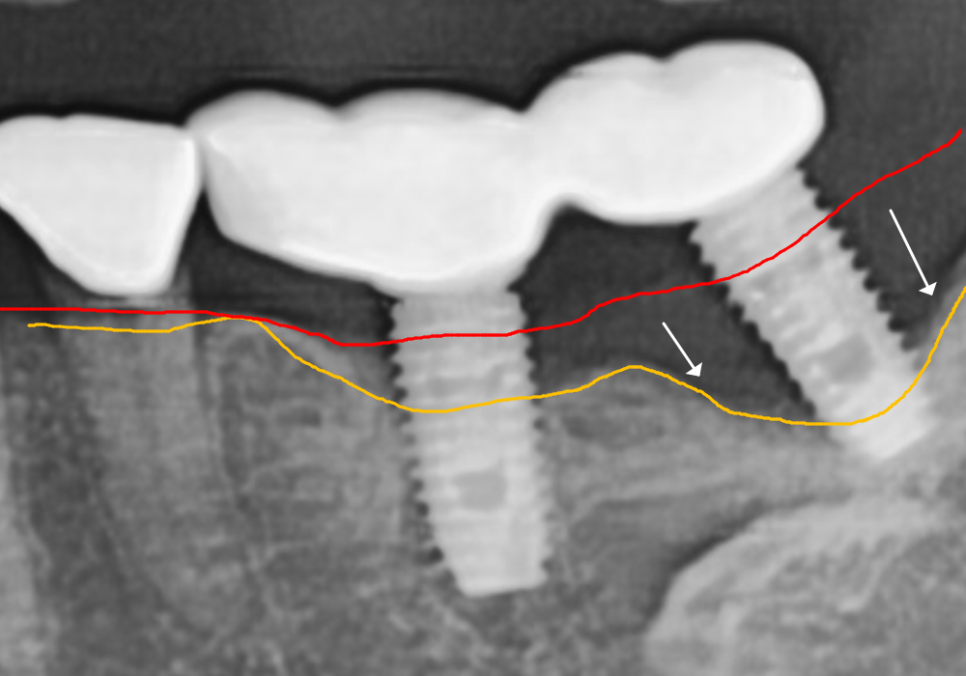

보통 이 정도로 뼈가 녹으면

임플란트가 심하게 흔들려야 정상이에요.

하지만 이 환자분은 앞뒤 임플란트 보철물을

하나로 묶어놓았기에,

망가진 임플란트가 앞쪽 임플란트에

고정되어 있어 흔들림을 전혀 못 느끼셨던 것이죠.

통증도 없고 흔들리지도 않으니

뼈가 다 녹을 때까지 모르고 계셨던 거예요.ㅜㅜ